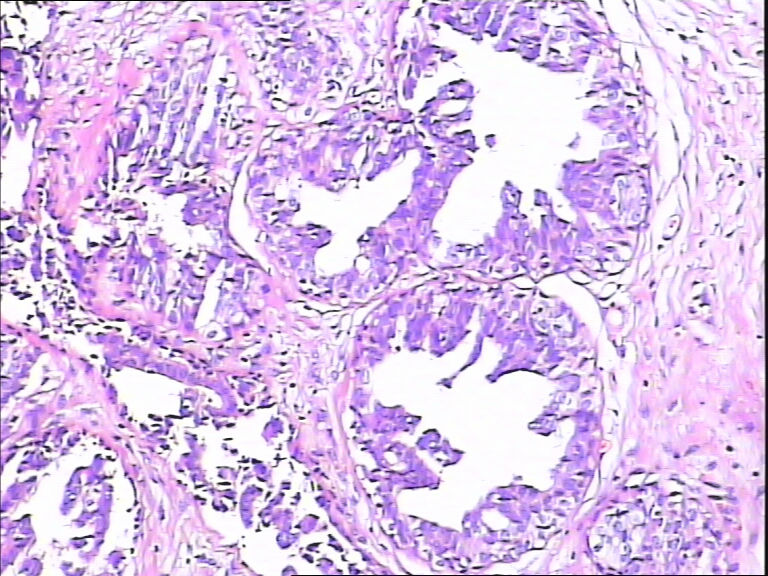

B3862乳腺包块

40岁,发现乳腺包快5月

标签:UDH ADH

觉得像UDH,做CK5,P63,UDH CK5腺上皮阳性,ADH CK5腺上皮阴性

ADH

DIN1b

导管不典型增生,不够导管内癌,做一做免疫组化就一目了然了

感觉不是普通型增生(UDH),应该到ADH或DCIS  免疫组化 ck5/6  34bE12

导管内癌

觉得不够癌

考虑导管内原位癌  需做组化确诊

Quality of the slides is not good.

More like UDH